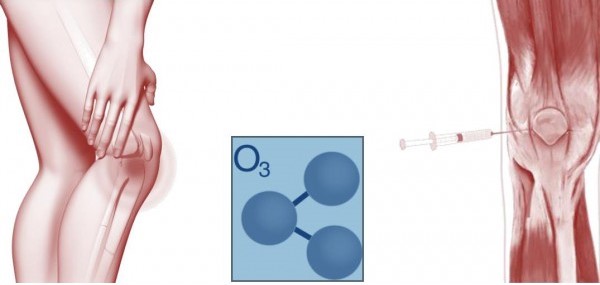

اوزون درمانی آرتروز زانو

اوزون(Ozone)؛ با فرمول O3 یک نوع گاز ناپایدار بوده و یکی از شکل های مولکولی اکسیژن هست. ازون دارای خاصیت اکسید کنندگی هم دارد که باعث می شود تا کاربرد های صنعتی زیادی هم داشته باشد.

اوزون تراپی یا اوزون درمانی یک روش درمانی با اوزون هست که در رشته های مختلف پزشکی مورد استفاده قرار می گیرد.

ازن درمانی استئوآرتریت زانو موجب کاهش درد زانو و بهبود عملکرد بیماران می شود. در این روش ازن به داخل مفصل زانو تزریق می شود، این کار معمولا در چند جلسه هفتگی انجام می گیرد.

البته درمورد ازون درمانی بحث ها و چالش های زیادی مطرح هست و برخی مطالعات آنرا موثر نمی دانند و این چالش ها در مورد ازن درمانی دیسک کمر و گردن بیشتر مطرح هست.